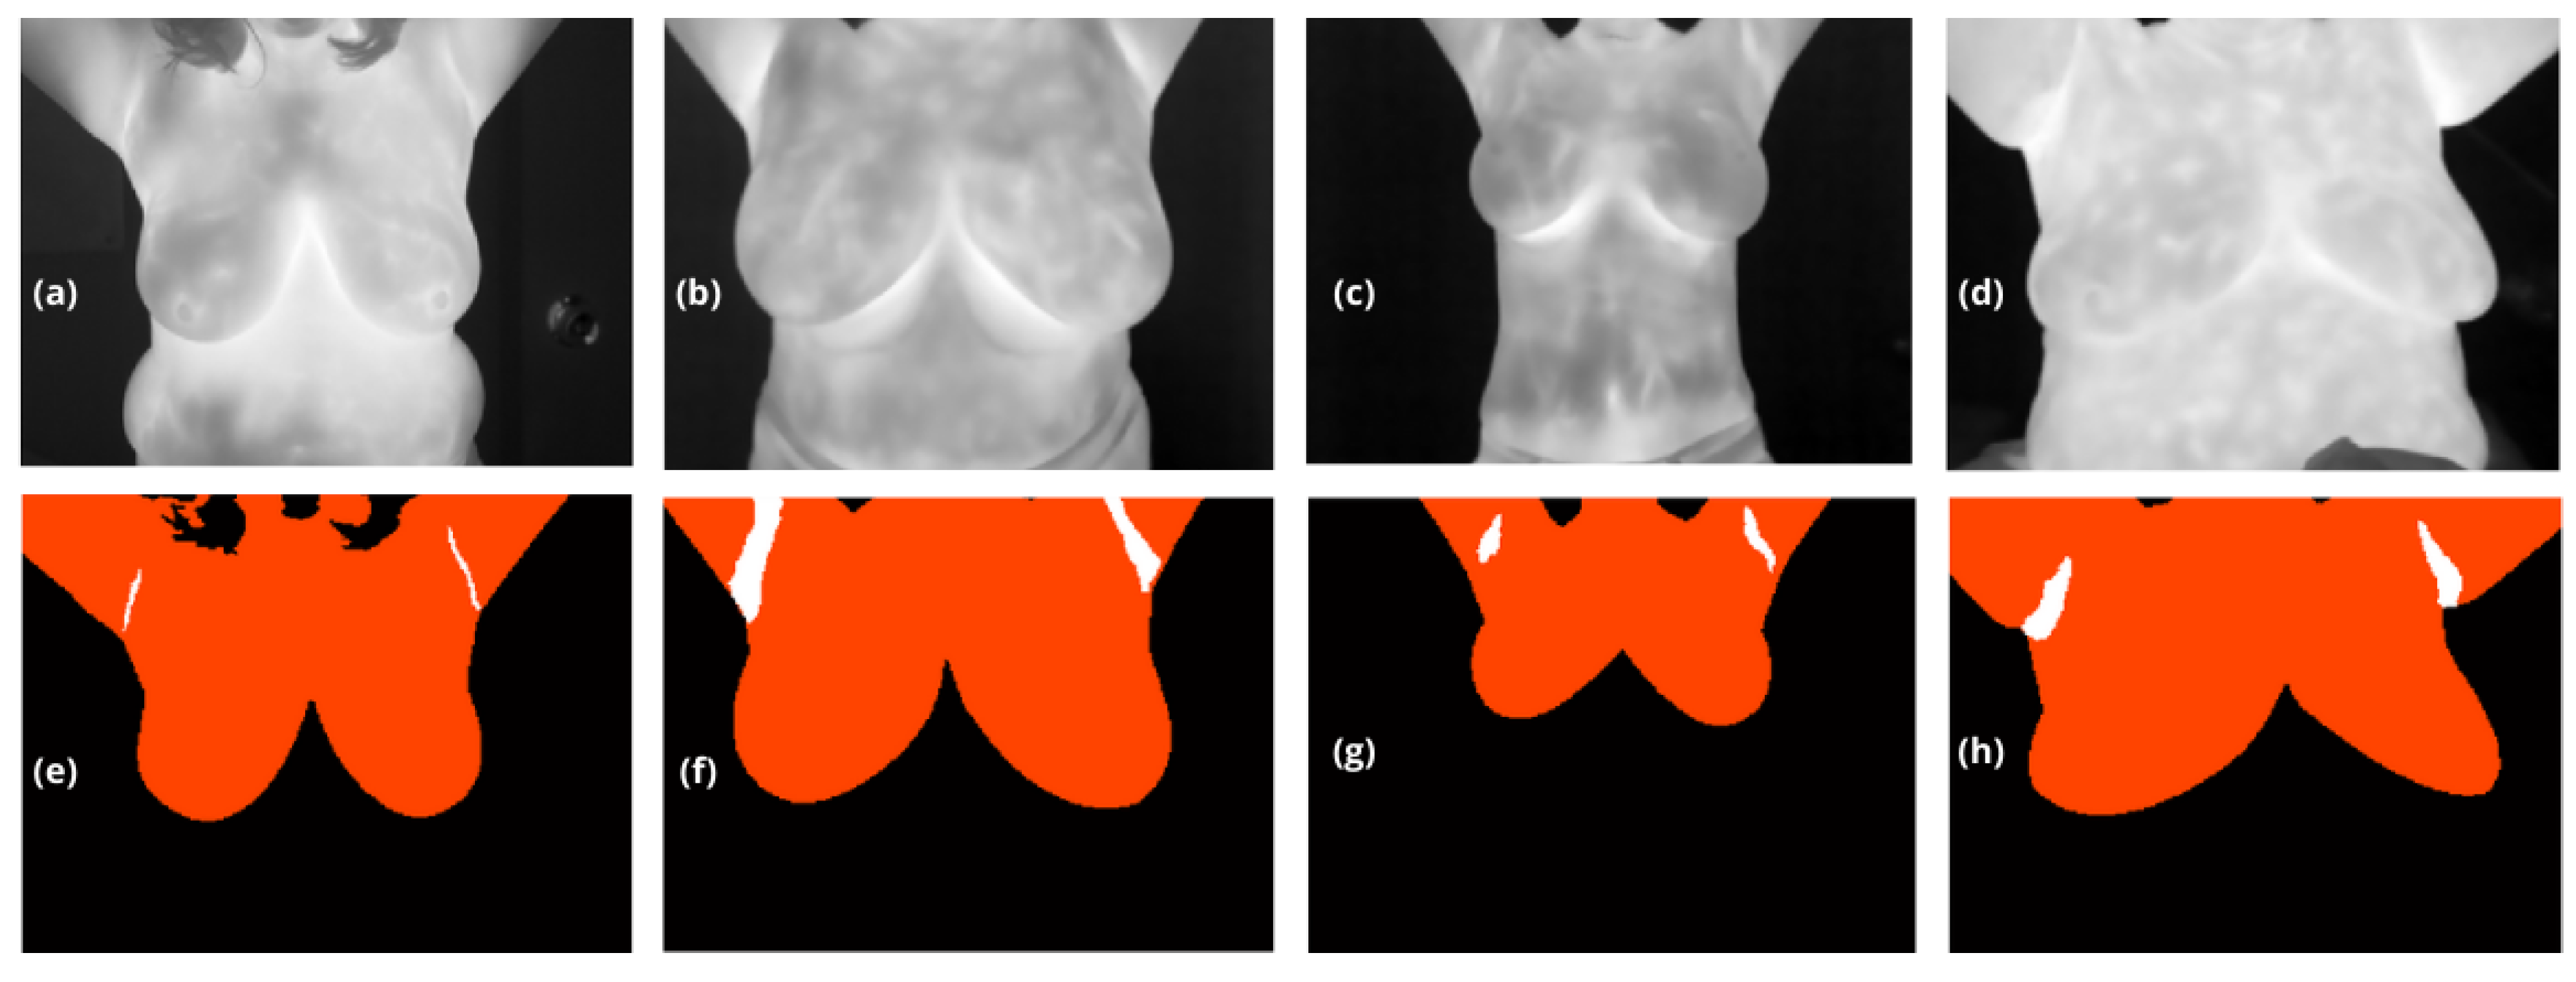

The output of this model is a multiclass segmentation mask, denoted α m a s k ( b g , b r , a r ) that distinguishes between the background ( b g ), the breasts ( b r ) extending from their lower boundary to the upper limit of the body with no constraints except for the lateral edge), and the armpits ( a r ), see Figure 2.

Figure 2. (a) to (d) thermographic images obtained from the dataset used for training, and (e) to (h) are their corresponding masks, α m a s k ( b g , b r , a r ) . In these masks, class 1 represents the background, marked in black α m a s k ( b g ) ; class 2, α m a s k ( b r ) , corresponds to the upper breast region up to the neck, marked in orange; and class 3 α m a s k ( a r ) , shown in white, represents the axillary regions.